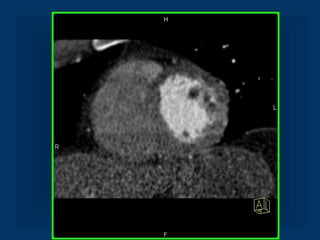

• Patient with crushing chest pain

• now relieved (Nitro)

• Borderline ST- Elevation

• No biomarker elevation

Patient with ACSPatient with ACS

• Patient withcrushing chest pain • now relieved (Nitro) • Borderline ST- Elevation • No biomarker elevation Patient with ACSPatient with ACS